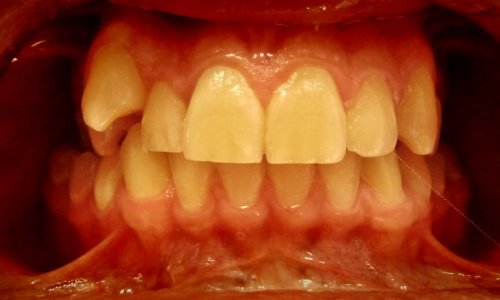

Zbliżenie Przed

Ustawienie Zębów

Stan wyjściowy: Pacjent zgłosił się z problemami estetycznymi i czynnościowymi zgryzu.